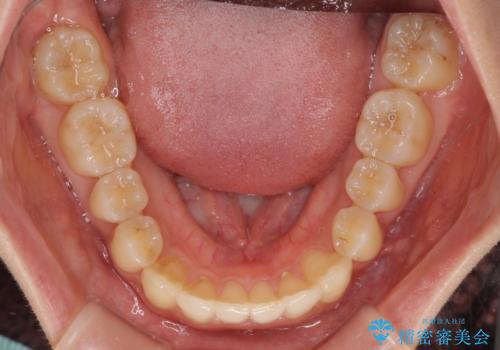

反対咬合が改善され、食いしばり癖もなくなり、顎関節の負担が軽減されました。

上顎骨を拡大したことで前歯に隙間ができ、1ヶ月ほど恥ずかしい時期がありましたが、しっかりとした咬み合わせに仕上がり、患者様には大変満足していただきました。